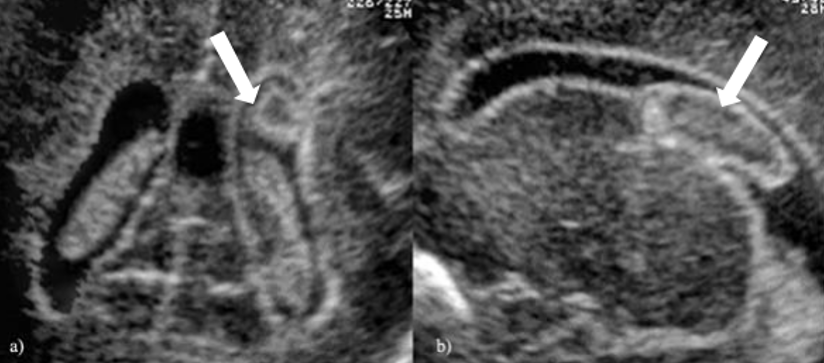

新生儿及小婴儿由于囟门未闭,给超声检查提供了非常好的声窗,可以藉此窥视患儿颅内的病变。由于其安全、无辐射,目前已成为临床小宝宝颅脑首选的检查方法。

划重点!只要囟门未闭,颅脑超声检查无绝对禁忌证,不多说,直接上图直观感受下,律动的囟门下,智慧的脑袋长啥样!

二、并发症:脑积水